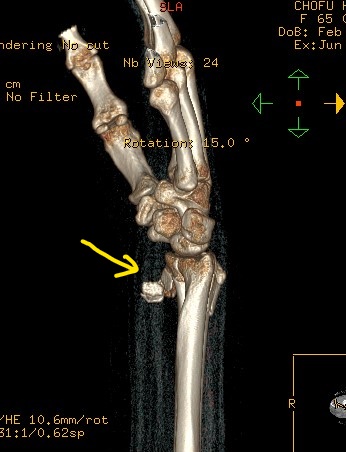

〇左前腕骨骨折(スミス骨折)

4件の整形外科をめぐり最終的に当院の保存治療を選択されました。

一件目の整形外科では足が専門なので断られシーネと包帯をしてもらいました。次に訪れた整形では手術が必要と大学病院を紹介

大学病院ではレントゲンの確認後、患部の手を触ることなく手術の日程を入れられました。手術に不安があった患者さんはインターネットで調べ手の専門整形外科を訪れました。そこでも手術を勧められ明日にでも処置をすると予定を強要されました。

しかし患者が不安を抱くのは手術だけではありません。どの医師も患部を診た触ることなしに当初巻かれた包帯のままでレントゲンを見るだけでした。そのため当初の包帯はぐじゃぐじゃ。たとえ手術の予定を入れたとしても包帯の巻きなおしが必要だったのではないでしょうか? これでは信頼できません。

当院はインターネットで知り来院されました。本人の強い意志と希望により当院で保存的に治療しています。経過は良好です。